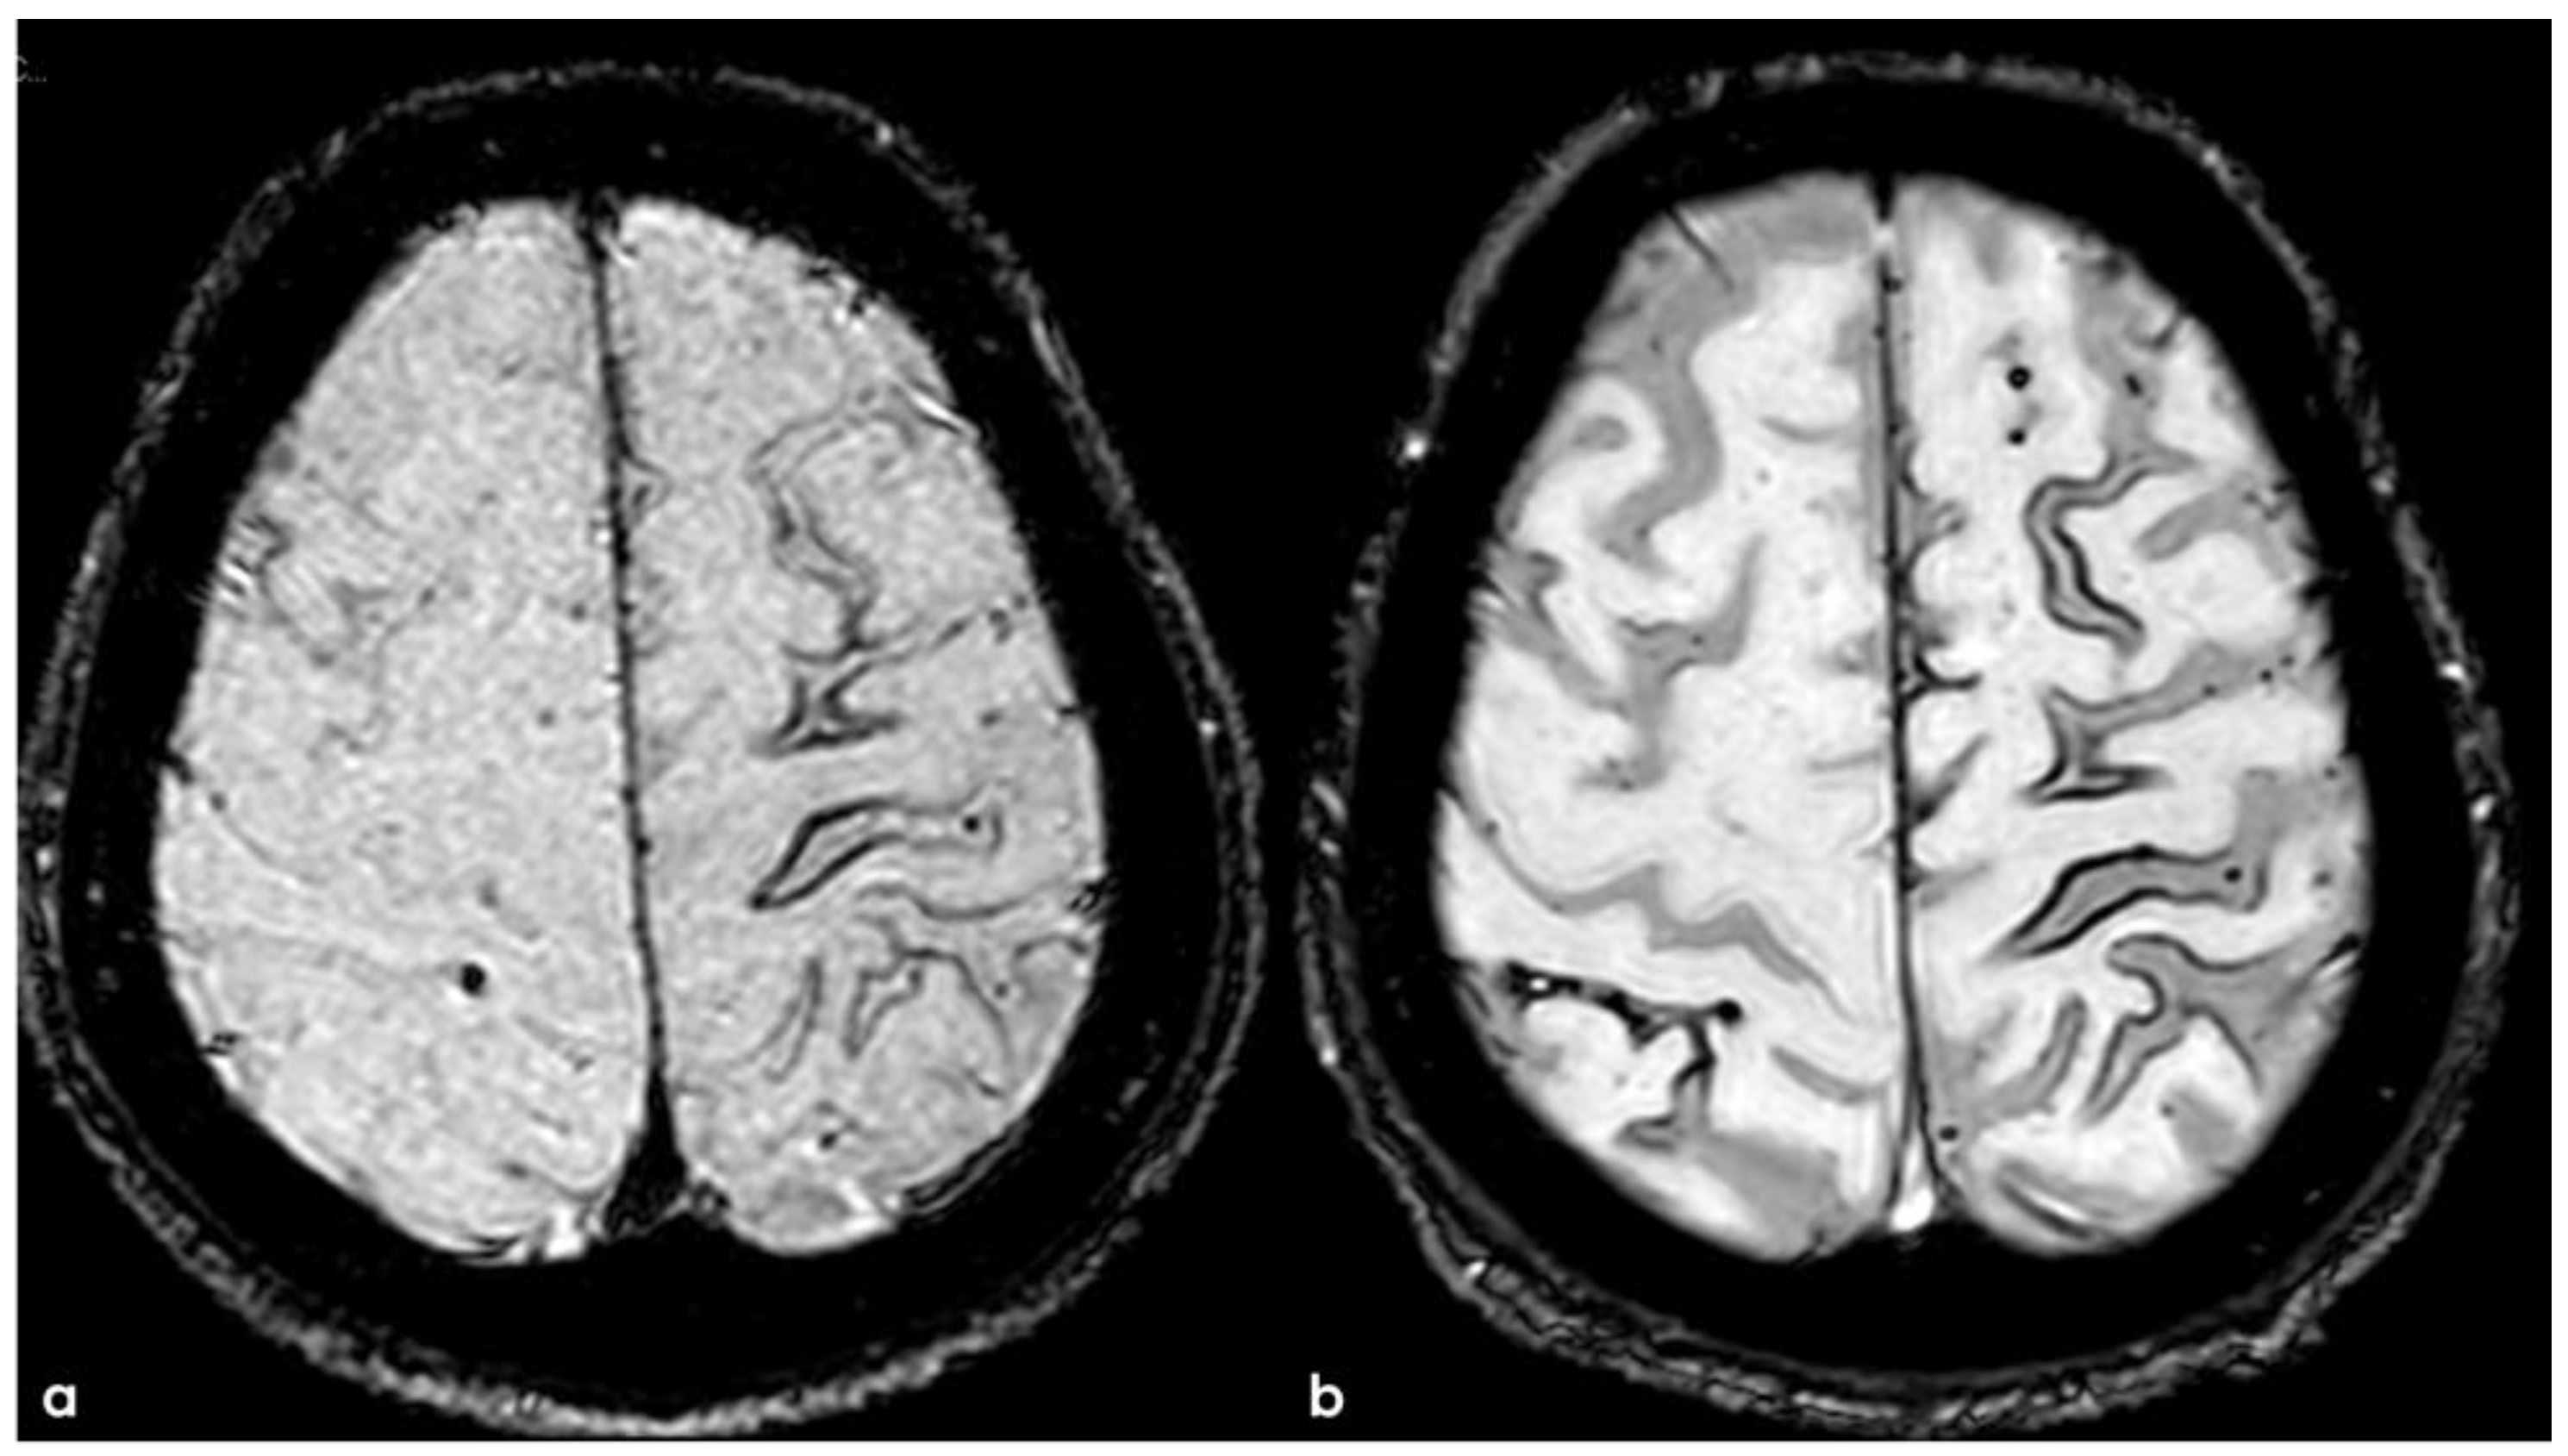

6. December 2017: Recurrent SAH

7. April 2018: Second Recurrent CAA-Related Inflammation